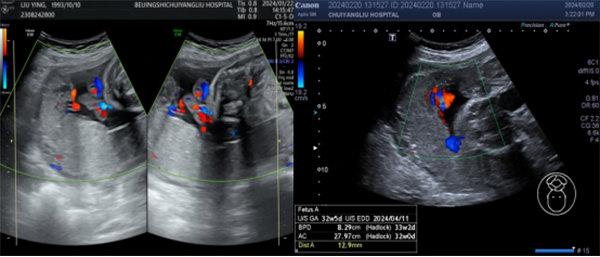

胎盘下缘与子宫颈内口的相对位置关系随妊娠及产程的进展而变化称为胎盘迁移。如树根在干涸的地方会枯萎或深扎,向水和营养丰富的区域延伸扩展。如图2-3所示,同一孕妇胎盘位置改变,其胎盘位置从早孕期的前壁宫底到孕晚期后壁为主,胎盘脐带插入点从相对正常位置发展成脐带位于胎盘边缘处的球拍状胎盘。有可能就是在迁移过程脐带插入点一侧胎盘逐渐萎缩。

▲孕28+周、孕32+周 后壁胎盘,脐带插入点位于胎盘上缘边缘处